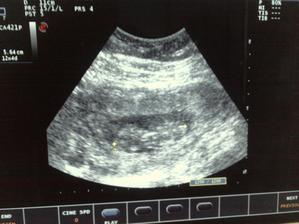

Naše druhé srdiečko 🙂

a je to tu, čakáme naše druhé bábätko, veľmi sa naňho všetci tešíme 🙂